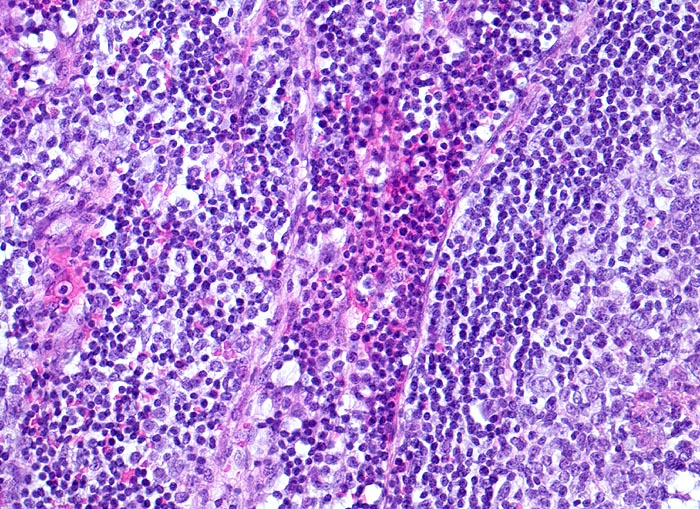

reaktive lymphatische Hyperplasie bei Katzenkratzkrankheit

Lymphknoten, Axilla

Das Lymphknotenparenchym ausserhalb der retikulozytär abszedierten Läsionen zeigt eine reaktive Hyperplasie mit Ausbildung von Sekundärfollikeln (Anschnitt eines Keimzentrums). Links davon die interfollikuläre Zone mit einem Sinus, welcher mit Entzündungszellen gefüllt ist (Bildmitte).

Druckschmerzhafte Lymphknotenvergrösserung in der rechten Axilla 2 Wochen nachdem der Patient von seiner Katze an der rechten Hand gekratzt wurde.

Histologie

200